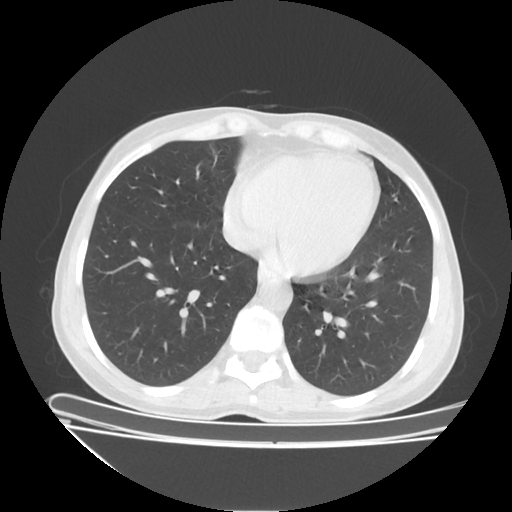

Original VENOUS CT scan

Full window (WL 1023.5, WW 4095 β†’ Low βˆ’1024, High +3071)

Actual HU range: [-1024.0, 1080.0]

Lung window (WL -600, WW 1500 β†’ Low βˆ’1350, High +150)

Actual HU range: [-1350.0, 150.0]

Mediastinum window (WL 40, WW 400 β†’ Low βˆ’160, High +240)

Actual HU range: [-160.0, 240.0]